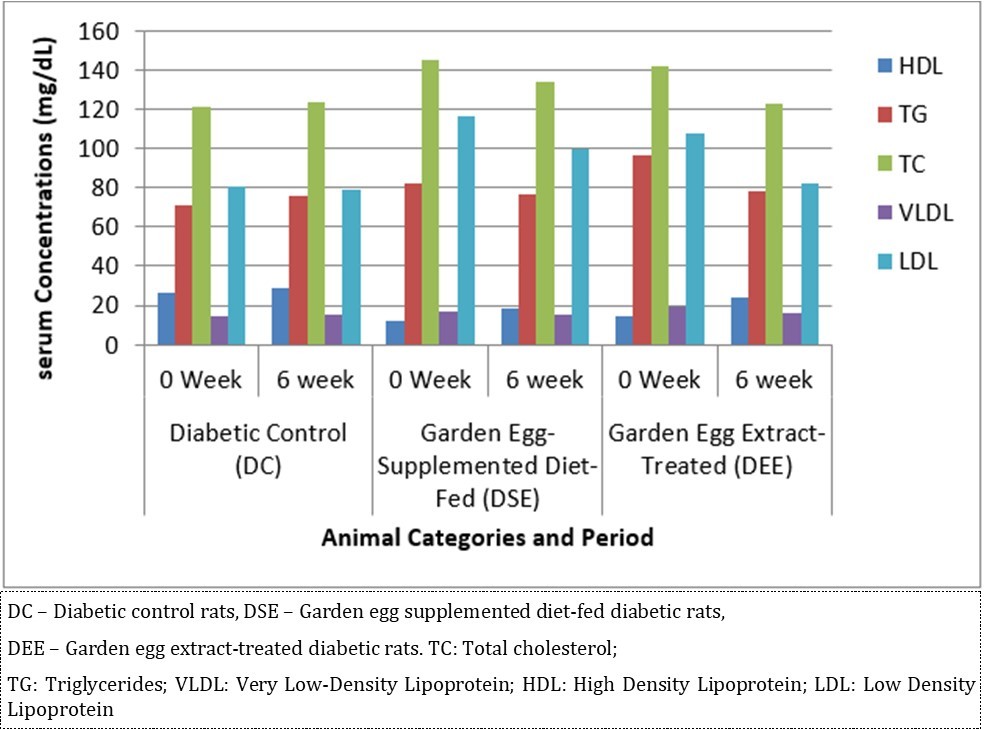

Effect of S. aethiopicum consumption on serum lipid parameters is expressed in Figure 3. At the end of the study, it caused significant (P < 0.05) decrease in TC, TG and LDL concentrations with corresponding significant increase in HDL concentration in DSE and DEE rats (DEE > DSE) compared with DC. This study reveals that consumption of S. aethiopicum improves lipid profile in diabetic rats.

Figure 3.Effect of S. aethiopicum on lipid profile in diabetic Wistar rats (n = 5/group)

Due to different species of garden egg in nature, likelihood of variation in its effect on weight reduction is expected. There is an uncited claim by some nutritionists that green garden egg species works better for weight loss compared to other species. However, findings obtained in our study using the white species with green stripes (S. aethiopicum L) revealed a remarkable reduction in weight gain in diabetic rats. Though, our present study did not compare species effect on weight gain, in our subsequent research however, we shall conduct a study to correlate species and weight-lowering effect. Meanwhile, based on the present outcome of this study, recommendation of the white-with-green-striped species should be encouraged for beneficial optimal effect on weight reduction. The beneficial impacts of S. aethiopicum on glycemic status and profile are depicted in Table 3 and Figure 2. The mean FBS concentrations decreased significantly (P < 0.05) in both DEE and DSE groups (DEE >> DSE, P = 0.025) compared with the control. The observed difference in their values was similar in manner to its effect on weight gain. The glycemic tolerance improved remarkably in both groups. This antidiabetic potential may be attributed to a major phenolic compound called chlorogenic acid (5-O-caffeoyl-quinic acid; CGA) present in garden egg 13, 21. Bhaskar 13 and Plazas 21 studies revealed that chlorogenic acid possessed anti-obesity, anti-inflammatory, anti-diabetic and, cardio-protective properties. The incremental areas under the glycemic response curves of DEE and DSE rats decreased remarkably compared with the control (Figure 2). The postprandial glycemic response peaked at 30 minutes of glucose challenge in both groups. The TC, TG and LDL-C concentrations decreased significantly with corresponding significant increase in HDL concentration in DEE and DSE rats (Figure 3). However, the extract impacts more beneficial antilipidemic effect than the supplemented diet. This finding also suggests that the optimal antilipidemic effect can be derived when S. aethiopicum is consumed in fresh or raw form than in mixed meal. The antilipaemic effect of eggplants has been attributed to an important phytonutrient compound called anthocyanin found in abundance in the skin of the eggplant which was reported to improve lipid profile through lipid peroxidation and serum antioxidants concentrations increase 27. Besides this antilipaemic activity, anthocyanin has also been reported to play significant role against diabetes, neuronal problems, cardiovascular disorders, and cancer as well 30. The pancreatic tissues sections’ photomicrographs examined under high power magnification (x 400) light microscope revealed the effects of S. aethiopicum on pancreas histoarchitecture. Figure 4 shows the normal appearance of the pancreatic histoarchitecture obtained from a healthy non-diabetic Wistar rat. Comparison of the experimental grouped rats photomicrographs with the normal revealed that the histoarchitecture of the pancreas in DEE and DSE (Figure 5, Figure 6) rats were preserved with no visible pathologic changes while the photomicrograph of the pancreas from diabetic control (DC) rats (Figure 7) shows distorted Islet margin with lymphocytic cells infiltration and moderate necrotic parenchyma. Examining the histological consequence of any product prior to recommendation is very essential because histological analysis of target organs for pathological changes surveillance is necessary to enhance screening assessment of quality and safety of product prior to recommendation for human consumption 31